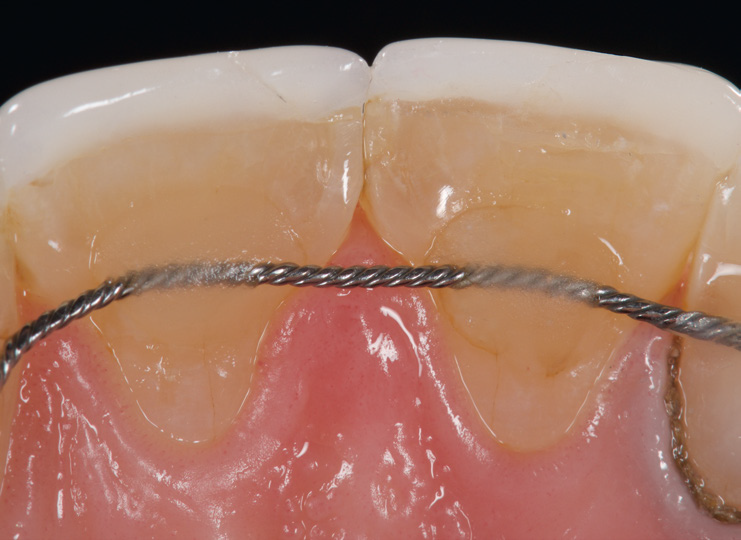

Palatal view showing incisal edge crack of veneer on tooth 11.

Final preparations.